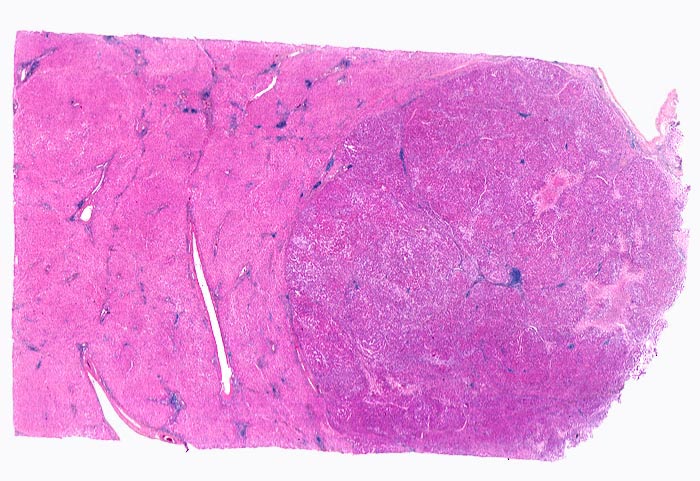

Makroskopisch imponiert das hepatozelluläre Karzinom als solitäre grosse Tumormasse, als zahlreiche zirrhoseartige Knoten oder als scharf begrenzter Knoten mit oder ohne Kapsel. Die tumorfreie Leber ist in der Mehrheit der Fälle zirrhotisch umgebaut. Mikroskopisch bilden die Tumorzellen mehr als 2 Zellen breite Trabekel (> 1237), kompakte Tumormassen (> 1229) oder pseudoglanduläre Strukturen (dilatierte Canaliculi) (> 1212) (> 1199). Desmoplastisches Bindegewebe fehlt meist. Innerhalb des Tumors fehlen Portalfelder. Es finden sich lediglich Arterien. Etwa bei der Hälfte der Karzinome lässt sich intrazytoplasmatische oder intracanaliculäre Galle (> 1238) nachweisen. Immunhistochemisch lassen sich mit einem polyklonalen Antikörper gegen Carcinoembryonales Antigen (CEA) Gallecanaliculi zwischen den Tumorzellen nachweisen. Die Tumorzellen bilden keinen Schleim.

• Die Tumorzellen bilden Trabekel, welche überwiegend mehr als 2 Zellen breit sind und Pseudodrüsen.

• Sinusoidartige Blutgefässe mit Endothelauskleidung verlaufen zwischen den Trabekeln und den Pseudodrüsen.

• Tumorfreies Parenchym mit chronischer viraler Hepatitis (B und D): dichtes chronisches Entzündungsinfiltrat in den Portalfeldern übergreifend auf das Parenchym (Interfacehepatitis). Spärliche intralobuläre Entzündung mit Einzelzellnekrosen (Apoptosen). Fibrose der Portalfelder mit Septenbildung und unvollständigem zirrhotischem Umbau.